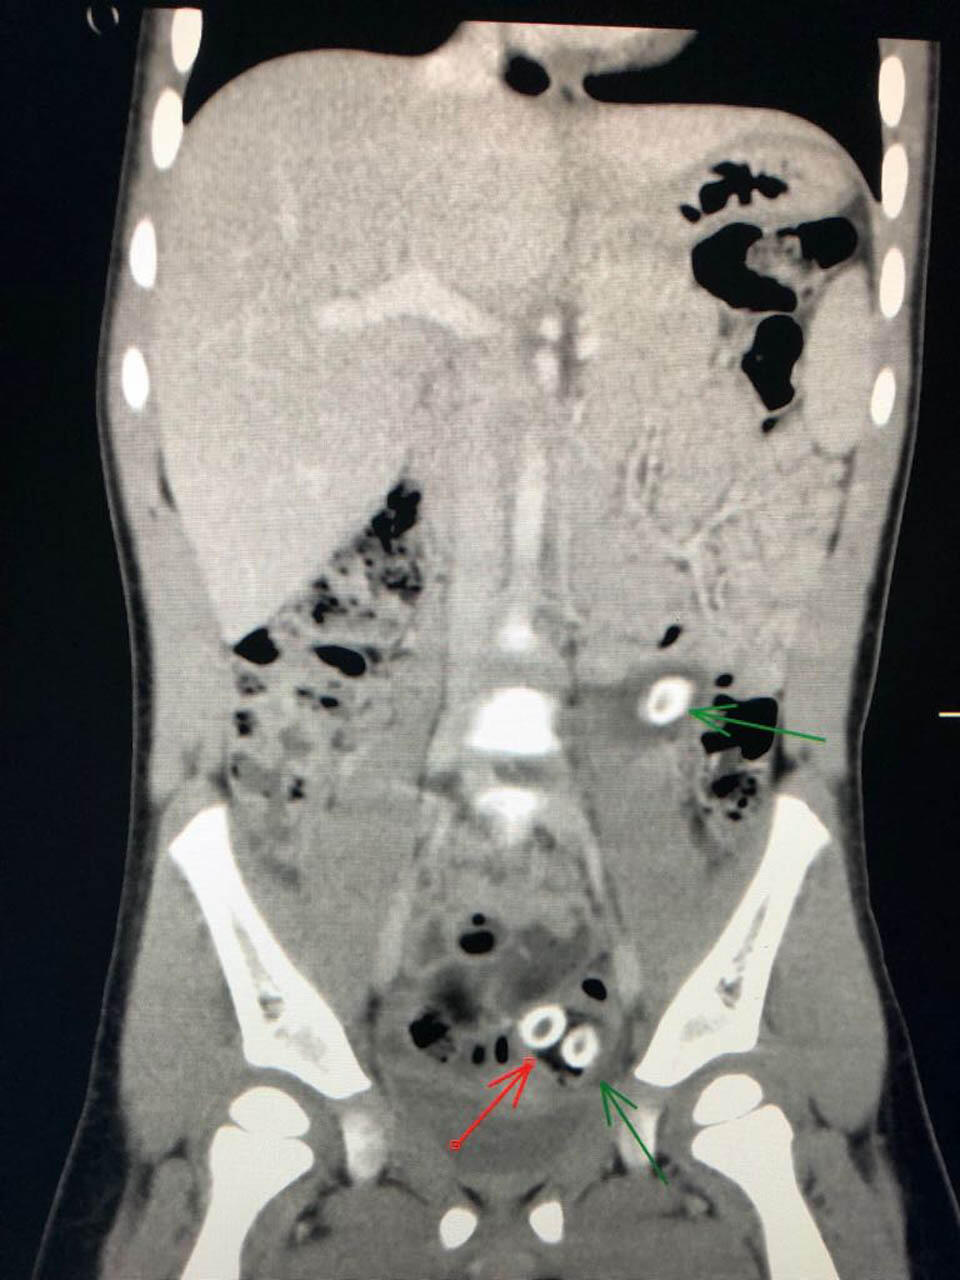

Рентгеновский снимок, стрелкой обозначены косточки от оливок. Фото: "Шнайдер"

Поскольку большая часть инородных тел находилась в толстом кишечнике, было решено оставить малышку под наблюдением до выхода естественным образом. Через несколько часов девочка попросилась на горшок, и инородные тела вышли. Ими оказались косточки от оливок.